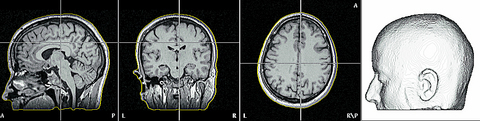

PHOTO COURTESY OF DAVID NIDDAM

With the MRI technology that looks deep into the brain, activity can be located to areas smaller than a millimeter, but cannot provide the temporal accuracy of an EEG or MEG. MRI works by tilting the spin of every atom in the body in the same direction, then sending pulses of radio waves into the scanner which knock the nucleus of each cell out of its proper alignment. When it realigns, it sends a signal which the scanner records, analyzes and drafts into an image.

Another form of MRI measurement, called a functional MRI, can measure brain activity by detecting oxygen levels in specific brain areas.

Niddam's colleague, Yeh Tzu-chen (葉子城), showed the MRI scan of a patient with a brain tumor. The functional MRI, he explained, is used not only to pinpoint the location of the tumor, but to discern what functions the areas of the brain beside the tumor control.

Because of the tumor's location on the left side of the patient's brain, there was a risk that surgery could leave the patient without the use of the right hand.

"During the MRI, I stood next to the patient and tapped on their foot," said Yeh, who is also an assistant professor in the Department of Radiology at National Yangming University Medical School. "They knew that when I did they should move their right hand. The MRI recorded exactly which part of the brain next to the tumor was responsible for moving the hand, creating an indispensable map for surgeons to use in removing the tumor."